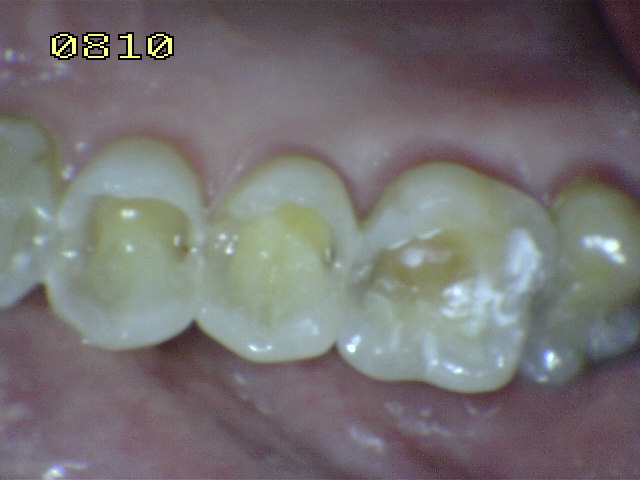

Si los mecanismos de la desoclusión no se se encuentran presentes en

la oclusión habitual (OH) del paciente (ver fotografías debajo), se

le explica el problema al paciente y se mantiene una conducta

En apariencia una relación

canina normal (guía anterior)

Observe el desgaste del canino inferior,

que no cumple la función de guía canina, y la función de

grupo posterior de premolares y hasta del primer molar. |

Por falta de guía canina en el lado de

trabajo, hay un desgaste de los bordes incisales del lateral

y central |